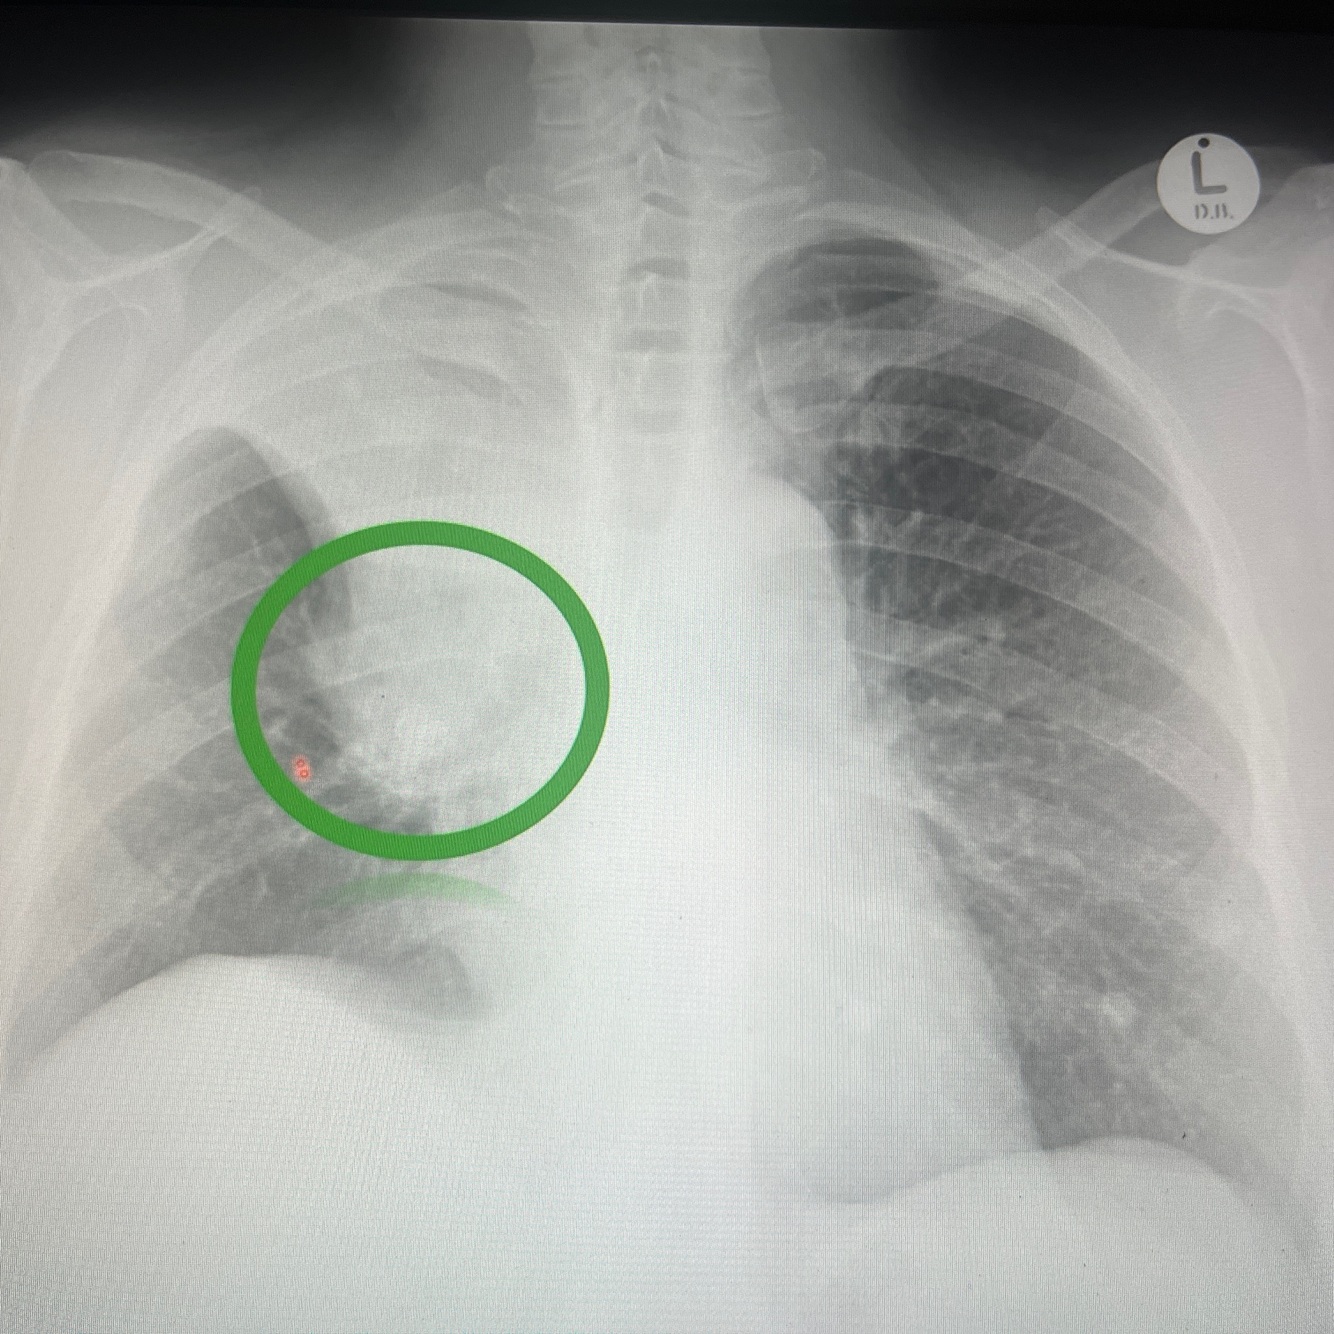

Golden s signs due to right hilar mass